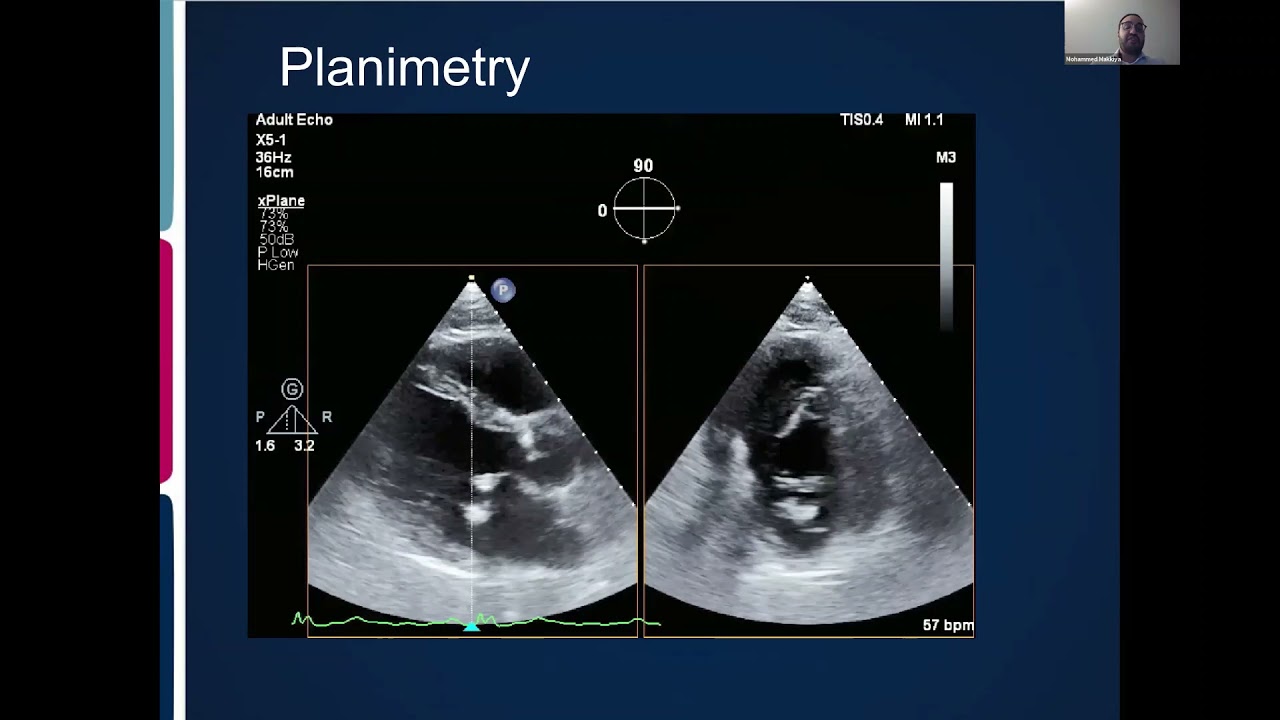

Joint Echo Conference: Mitral Stenosis

E3 is now hosting a bi-weekly lecture series that provides a platform for early career cardiologists, sonographers, or trainees to present and discuss echocardiographic topics. This lecture is on Mitral Stenosis.